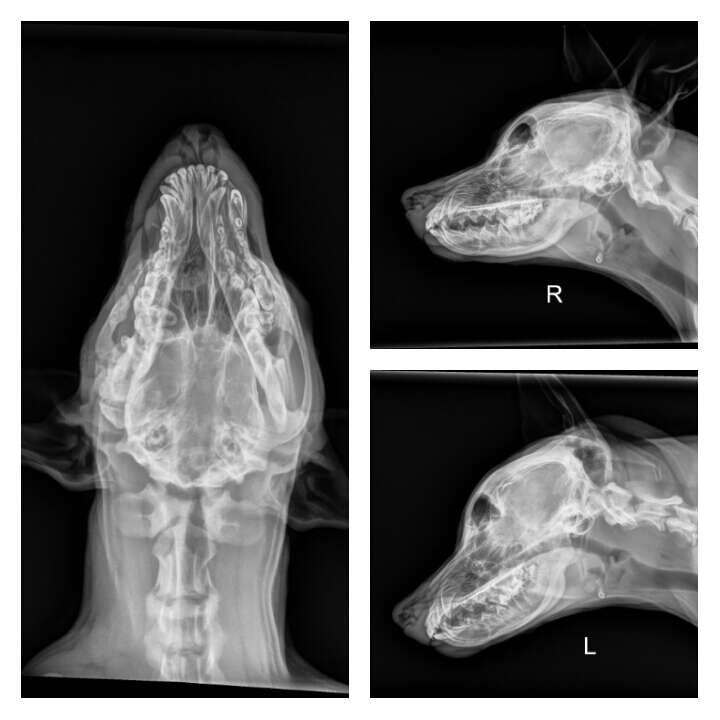

Before the final appointment, a team of specialists decided to take one last look. The results of a CT scan were chilling. Squish hadn’t been bitten by another dog. Instead, his skull and upper jaw had been fractured by a severe, intentional blow to the head. He had been a victim of unspeakable cruelty, and the resulting scar tissue had fused his jaw shut as he grew.